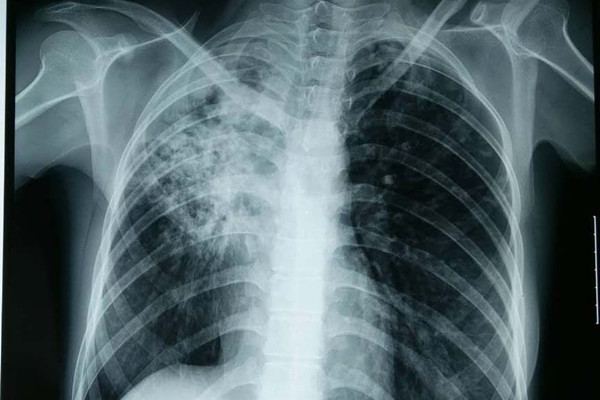

关于肺结核我们了解到这是一种由结核分枝杆菌感染引起的一种经呼吸道传播的慢性传染病,排菌的肺结核患者是结核病的主要传染源,肺结核传染性的大小与患者病情的严重程度、排菌量的多少、咳嗽的频度、房间的通风情况及接触者的密切程度和机体抵抗力有关。